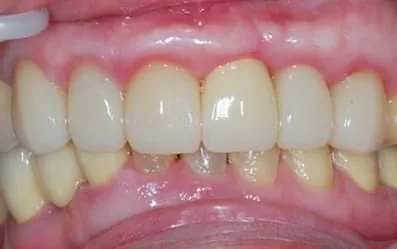

治療後:微創立即植牙恢復美麗外觀

製作全瓷冠,是不是完全看不出來曾經接受2顆植牙呢!

比較最初與植牙後的X片,可見到左邊與自然牙間完整保留原來的骨質(水平線),右邊與植牙間更誘導再生出更多的骨質(箭號),如此牙齦不會萎縮,才能塑型到漂亮。